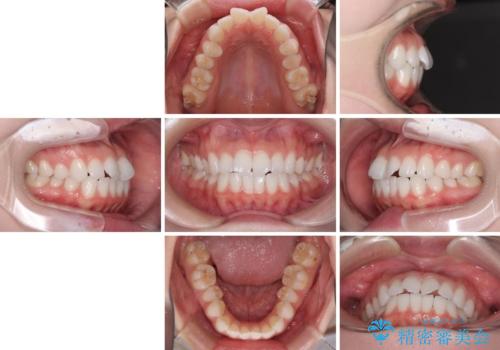

- 海外留学を前に上下のデコボコと奥歯の咬み合わせを改善したいとのことで来院された患者様です。

期間が限られていたため、ワイヤー装置による矯正治療を行うこととしました。

治療開始から4ヶ月ほどで概ね歯列が整い、その後の3ヶ月で細かい部分を仕上げていきました。

短期間で綺麗に仕上がり、患者様には大変満足していただきました。